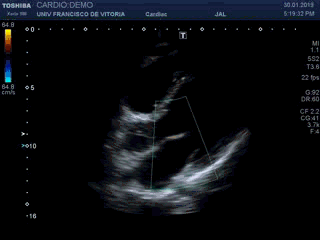

Por último, vamos a poner una caja de Doppler color (clip 2) para averiguar qué pasa con la sangre cuando circula desde la AI al VI y desde el VI a la Ao Asc; si lo hace en la dirección correcta o se mete por dirección prohibida en caso de una insuficiencia; y a qué velocidad si la válvula no se abre todo lo que debe (estenosis valvular). Respecto al Doppler, además de visitar el post correspondiente, recordad que cuanto más estrecha sea la caja de color, menos penalización habrá en términos de resolución temporal. No hay problema en la apertura de la caja en vertical. Y por otra parte, hay que adaptar la escala (me gusta más llamarlo escala que PRF, pero son manías mías) a las velocidades del corazón, que van a estar en torno a los 60-80 cm/s

Finally, we are going to put a box of color Doppler (clip 2) to find out what happens with the blood when it circulates from the AI ​​to the VI and from the VI to the Ao Asc; if it does it in the right direction or it gets in the prohibited direction in case of an insufficiency; and at what speed if the valve does not open as much as it should (valvular stenosis). Regarding Doppler, in addition to visiting the corresponding post, remember that the narrower the color box, the less penalty there will be in terms of temporal resolution. There is no problem in opening the box vertically. And on the other hand, you have to adapt the scale (I like to call it scale rather than PRF, but they are my hobbies) at heart speeds, which will be around 60-80 cm / s